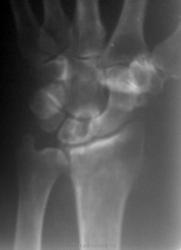

Киста и подвывих полулунной, помимо артроза.

Еще и старый консолидированный перелом лучевой кости

Полиартроз

Неоднозначно всё

Согласен со всем, окромя РА))))